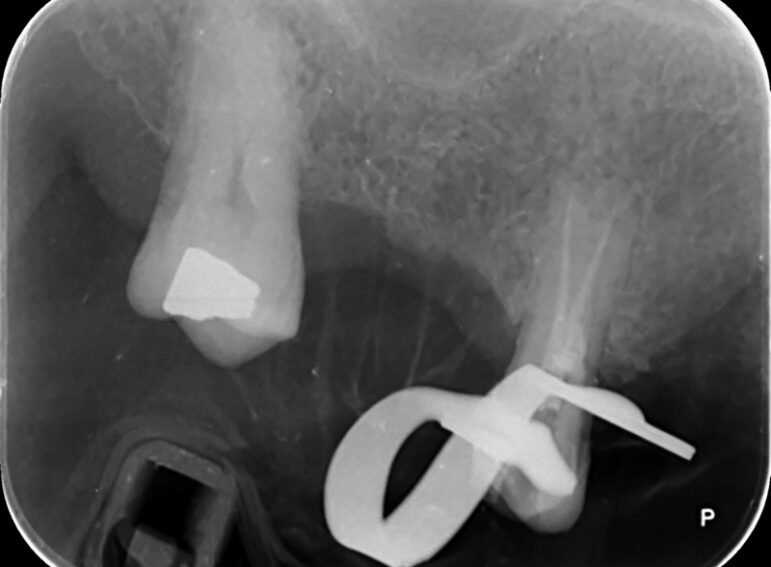

Case 18 – Endodontics

Perforation during root canal treatment and repair